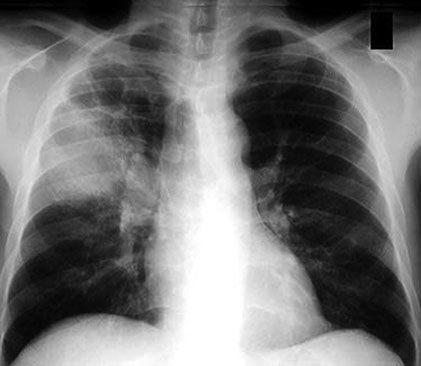

A 35‐year‐old refugee from Eritrea had a 4‐month history of night sweats and weight loss. Recently he had become more short of breath and had haemoptysis. He shared a room with four other family members. He has lived in the UK for 6 months. Though he remained haemodynamically stable he had a temperature of 38°C. Bronchial breathing was heard in the right upper zone of his chest. He had a mantoux test which was read 48 hours later and found to be strongly positive. He had a chest X‐ray (Fig. 0007) and his sputum showed acid‐fast bacilli.

Fig. 0007.